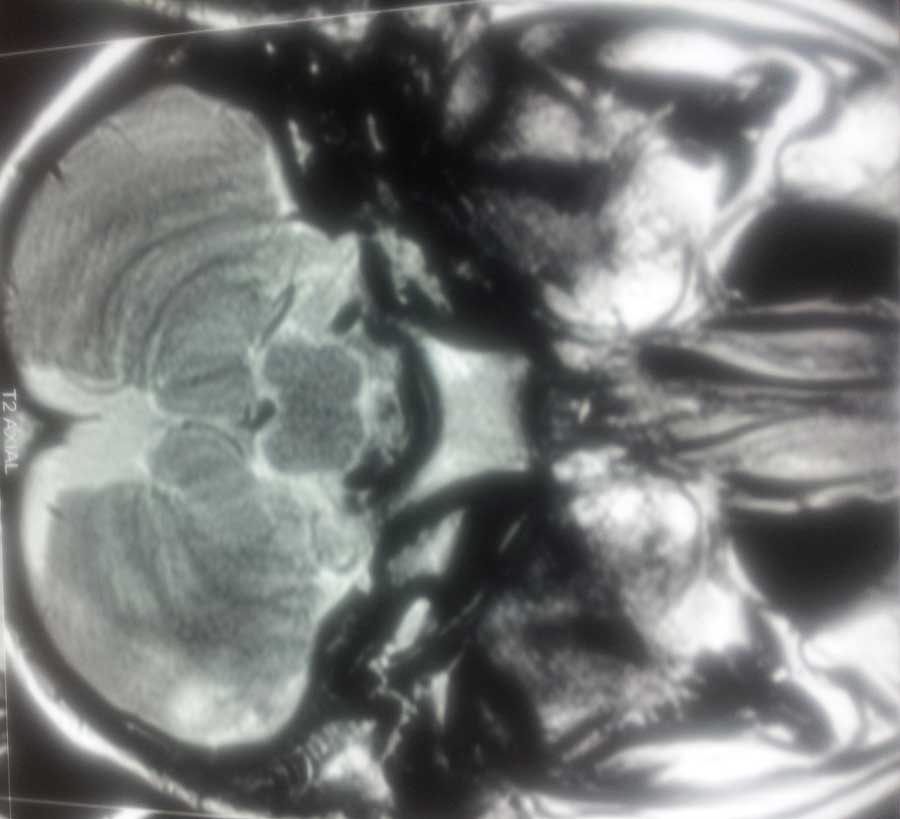

Brain Abscess Brain Abscess Post OP 2 Clinical Intra OP ,After Excising The Granuloma Intaop Scalp Abscess CT Scalp Abscess Cerebellar Abscess Post OP Clinical Cerebellar Abscess Brain TB Granuloma Post OP CT Scan Brain Infection Brain Abscess Preop MRI 2 Brain Abscess PRE OP Clinical 1 Brain Abscess PRE OP Brain Abscess Intraop 2 Brain Abscess Following Shunt Temporal Abscess T2W of TB Granuloma Scalp Abscess Preop CT Marking PRW OP MRI of TB Granuloma Post OP Clinical Photo Post OP Cerebellar Abscess Post OP Brain Abscess Intraop Specimen of Granuloma